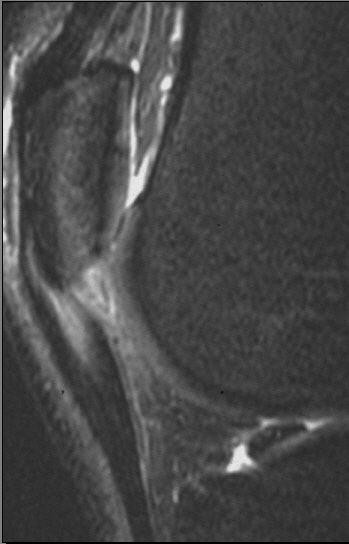

| Sagittal images of patellar tendinopathy or "jumper's knee" in a cyclist. Courtesy of Duke University Medical Center, Musculoskeletal Division, Durham, NC. |

How do cyclists get jumper's knee? "The repetitive flexion-extension process that goes around their knees can lead to strain on the patellar tendon," said Major, who sees many cycling athletes in her practice. "The tracking of that patella as it crosses the femur (causes) rubbing that can lead to problems in the joint space, and then with that tendon."